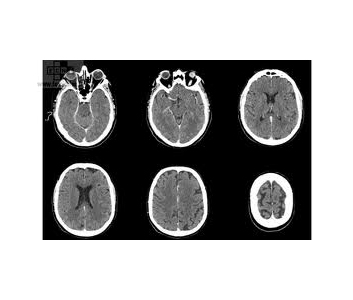

Le mince pinceau de rayon X permet d’effectuer des coupes avec une dose très faible, qui apparaissent sur un écran de télévision après avoir été reconstruites dans un ordinateur.